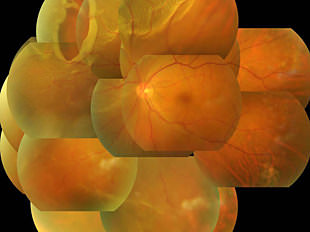

網膜静脈閉塞症

網膜静脈が詰まり、その先の静脈が拡張して蛇行し、眼底出血や浮腫が起きます。

出血や浮腫が黄斑部にかかると視力低下をきたします。

術前写真

術前 OCT

術後写真

術後 OCT